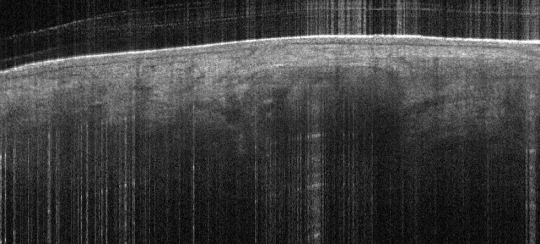

• Typically only the upper facing of the gland is seen

• The “hazy” granular texture of the gland’s cells is often surrounded by a darker hyporeflective border to the surrounding dermal collagen, which also isolates individual lobules of the gland